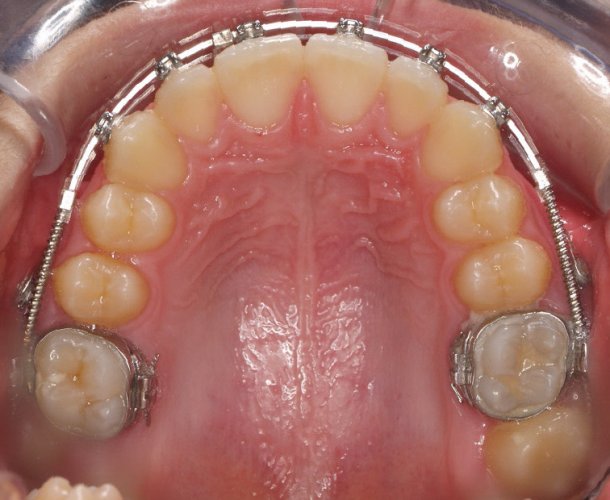

Paciente de 14 años, acude a nuestra consulta por dientes superiores proclinados hacia delante y apiñamiento. El paciente presenta una full clase 2, sobremordida y dientes inferiores proclinados. Decidimos colocarle brackets Damon y microtornillos en maxilar superior para distalizar las muelas. La duración del tratamiento fue de  24meses, y ahora lleva 1 año de contención. El paciente se pone la férula Essix superior 1noche/2 y la de abajo 1noche/semana para mantener.

03-04--076-Upper Occlusal-01012006